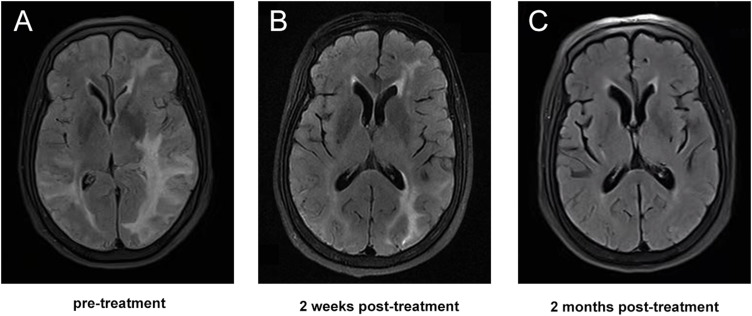

目的:本研究旨在分析一组脑淀粉样血管病相关炎症(CAA-ri)患者的临床表现、实验室结果、神经影像学特征、治疗干预及转归,以加深对这一罕见亚型CAA的认识,提高临床诊断的准确性。方法:对2021年1月至2024年8月郑州大学第一附属医院连续13例符合可能CAA-ri诊断标准并进行评估的患者的临床记录进行系统回顾性分析。结果:研究队列包括13例患者(男性7例,女性6例;平均年龄65.2岁(42 ~ 81岁),主要表现为亚急性发病(53.8%,n=7)。最常见的临床表现是认知障碍(61.5%,n=8),其次是头痛(46.2%,n=6)、癫痫发作(30.8%,n=4)和局灶性神经功能障碍(23.1%,n=3)。所有患者的神经影像学结果均显示不对称白质高信号并伴有皮质-皮质下脑微出血。一部分患者表现为皮质浅表性铁沉着、大叶出血和/或点状急性梗死。在接受腰椎穿刺的9例患者中,5例脑脊液(CSF)压力和蛋白水平升高。所有4例脑脊液阿尔茨海默病生物标志物评估的患者均显示Aβ42和Aβ40水平降低,同时总tau蛋白和磷酸化tau蛋白水平升高。此外,超过70%接受免疫抑制治疗的患者获得了良好的临床结果。结论:临床表现和神经影像学异常是指导临床医生诊断CAA-ri的关键非侵入性标准。CAA-ri患者及时开始免疫抑制治疗可导致良好的结果。

Results: The study cohort comprised 13 patients (7 males, 6 females; mean age 65.2 years, range 42-81), predominantly presenting with subacute onset (53.8%, n=7). Cognitive impairment (61.5%, n=8) emerged as the most frequent clinical manifestation, followed by headache (46.2%, n=6), epileptic seizures (30.8%, n=4), and focal neurological deficits (23.1%, n=3). Neuroimaging findings across all patients demonstrated asymmetric white matter hyperintensities in conjunction with cortical-subcortical cerebral microbleeds. A subset of patients exhibited cortical superficial siderosis lobar hemorrhage, and/or punctate acute infarction. Among the nine patients who underwent lumbar puncture, five showed elevated cerebrospinal fluid (CSF) pressure and protein levels. All four patients assessed for CSF Alzheimer's disease biomarkers showed reduced Aβ42 and Aβ40 levels, alongside elevated total tau and phosphorylated tau levels. Furthermore, over 70% of the patients who treated with immunosuppressive therapy achieved favorable clinical outcomes.

Conclusion: Clinical manifestations and neuroimaging abnormalities serve as pivotal non-invasive criteria for guiding clinicians in the diagnosis of CAA-ri. Timely initiation of immunosuppressive therapy in CAA-ri patients can lead to favorable outcomes.